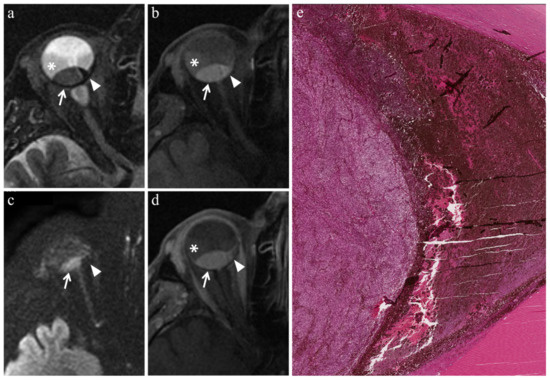

| Radiation-induced necrosis | ![]() Low signal | ![]() High signal | ![]() No enhancement | ![]() Low signal |

| Fibrosis | ![]() Low signal | ![]() Intermediate signal | ![]() Moderate enhancement | ![]() Low signal |

| Viable tumor tissue, pigmented melanoma | ![]() Low signal | ![]() High signal | ![]() Enhancement of viable tissue | ![]() High signal |

| Viable tumor tissue, poorly pigmented melanoma | ![]() Intermediate signal | ![]() Intermediate signal | ![]() Enhancement of viable tissue | ![]() High signal |